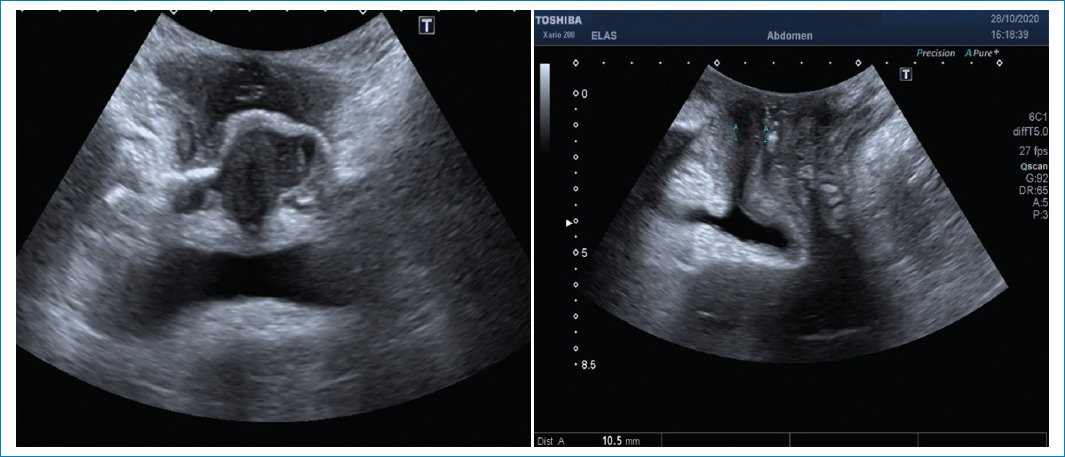

HIATO UROGENITAL

Se puede evaluar la medida del hiato urogenital observando si hay coactivación de los músculos del suelo pelviano cuando aumenta la presión intraabdominal en maniobras de Valsalva. Esta coactivación del elevador del ano puede estar relacionada con patologías como el vaginismo o el anismo. El tratamiento consiste en rehabilitación con kinesiología (Fig. 12).

Figura 12. Se observa un aumento del hiato urogenital en Valsalva, en relación con una correcta relajación del músculo elevador del ano en la imagen de la derecha y en la imagen de la izquierda, la coactivación del músculo elevador del ano en Valsalva.